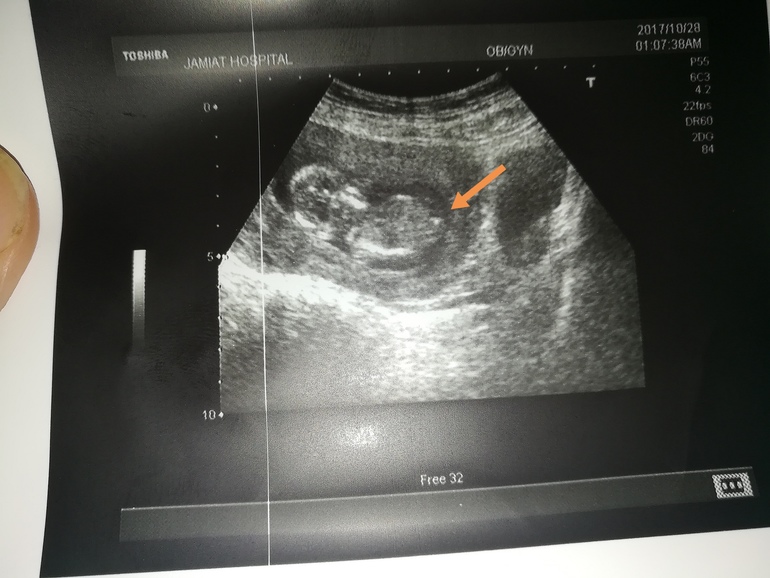

Пол малышаСрок 13+4. Узистка не стала даже предполагать кто, сказала,что на этом сроке легко ошибиться. Я попросила дать снимок "бугорка". Аппарат не важный был. Кто кого видит? То,что стрелочкой отмечено и есть половой бугорок?

На экране.часто мелькали вот эта беленькая точка, узистка сказала, что вроде торчит, но точно не скажет кто.